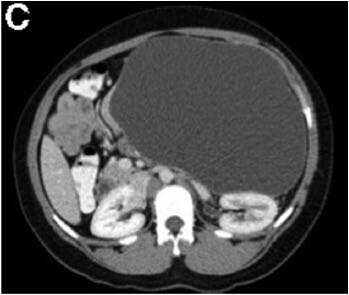

3个月前,她被电击中摔伤了腹部。当时这引起了上腹部疼痛;然而,她没有立即去医院直到3个月后才就诊。 该患者之前没有明显的病史或手术史,是一个非吸烟者,偶尔饮酒。 身体检查发现该女性健康,营养状况良好,唯一值得注意的是,腹部浅触诊时可于上腹部触及一个明显的肿块。 血常规检查包括全血细胞计数,尿素氮,电解质,葡萄糖,以及肝功能检查,均在正常范围内。血清淀粉酶66U/L,白蛋白43g/L,HIV 1/2 Ab/Ag酶联免疫吸附试验为阴性。 腹部对比增强计算机断层扫描显示连续轴向截面如图A-D。图E为矢状面。 剖腹手术时吸出低黏度,清澈,囊液,囊液生化分析显示,淀粉酶58903U/L,乳糖脱氢酶904U/L,蛋白质<10g/L。未获取囊性癌胚抗原和CA-19-9。在剖腹手术时对多个囊壁活检取样(图F)。

计算机断层扫描证实源自胰尾的一个大型,单房,囊性肿块,伴未分隔的附壁结节,或囊性钙化。影像学结果,临床病史,和囊液分析支持胰腺假性囊肿的诊断。出人意料的是,囊壁活检显示为良性粘液分泌柱状上皮,雌激素受体阳性,与良性粘液性囊壁肿瘤(MCN)一致。最终,执行远端胰腺切除术,并且此后恢复良好。鉴于MCNs已经确定的恶变可能(6%-27%的病例),这例患者“有惊无险”,按照计划因假囊肿接受胰囊肿胃吻合引流术可以避免恶性肿瘤转化的严重后果。